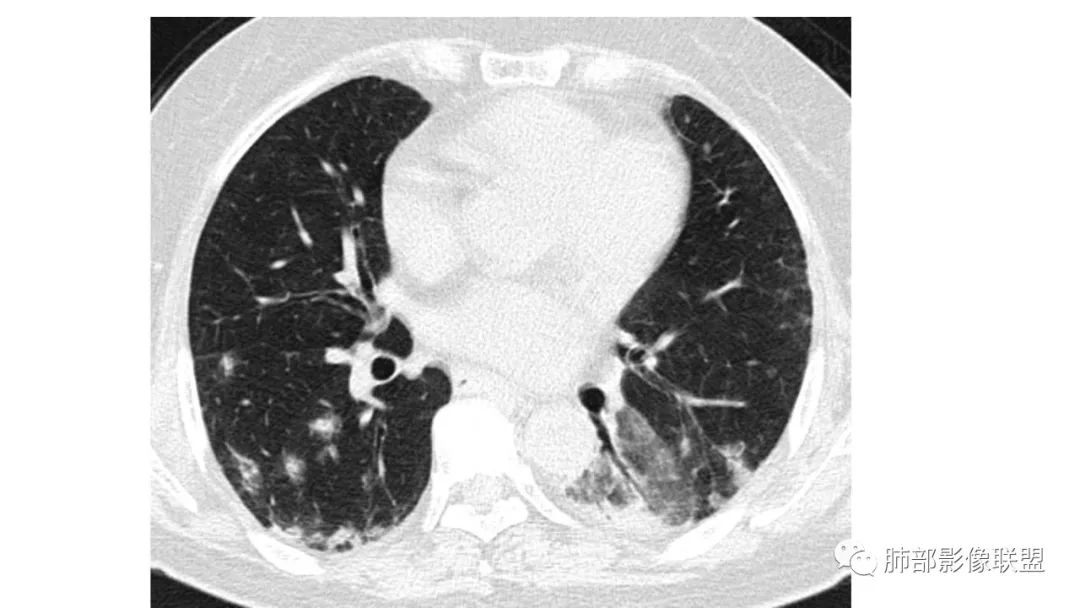

二、肺炎型

2、病灶常有一个主病灶,常位于下肺。后沿气道播散为多发病灶。

3、重力作用,叠瓦征。近叶间裂因重力效应,呈膨隆改变。

4、增强后不均匀强化,存在低强化区呈弱强化或无强化,因此可见“血管造影征。”血管毛糙与肺炎有统计学差异。

5、支气管粗细不均,呈“枯树枝征”,但与肺炎这一点鉴别不具有统计学差异。可发生支气管扩张

6、空腔形成,部分蜂窝状改变。

8、斑片常伴有结节,边缘清楚GGO或欠清楚。

4.回到本例,左下肺病变两次好转,均未经过肿瘤治疗,第一次是支气管镜后,第二次是当其他病变都在进展的情况下,左下肺病变范围反而缩小趋于浅淡。